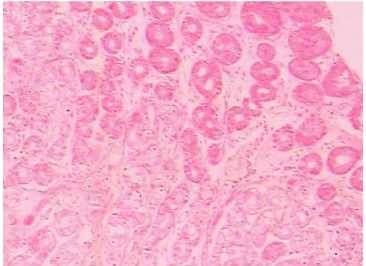

十二指腸潰瘍嚴(yán)重嗎

近年來,十二指腸潰瘍的發(fā)病率開始呈下降趨勢(shì),然而其仍屬消化系統(tǒng)疾病中最常見的疾病之一。十二指腸潰瘍的危害極其大,其并發(fā)癥輕則擾亂消化系統(tǒng),重則穿孔、癌變,導(dǎo)致死亡。

十二指腸潰瘍不及時(shí)治療會(huì)造成潰瘍出血,一般潰瘍病活動(dòng)期,病變均有微量出血,故糞便內(nèi)有隱血存在,這不足以稱為本癥的并發(fā)癥。所謂的潰瘍出血指的是一次出血量在60~100毫升以上的有明顯消化道癥狀的。主要表現(xiàn)有頭暈、脈速、面色蒼白、出冷汗及四肢厥冷、血壓下降等休克征象。若出血過多過快,甚至可危及生命。

其次,十二指腸潰瘍?cè)斐傻奈:τ袧兇┛?,潰瘍急性穿孔是潰瘍病最?yán)重的并發(fā)癥,約占潰瘍病的15%,也是潰瘍病致死的主要原因。

再者,十二指腸潰瘍?cè)斐傻奈:τ杏拈T梗阻,潰瘍發(fā)生于幽門部或十二指腸球部,容易造成幽門梗阻.有暫時(shí)性和永久性兩種同時(shí)存在。

最嚴(yán)重的時(shí)候,十二指腸潰瘍會(huì)有可能造成潰瘍癌變,胃潰瘍發(fā)生癌變多見于年齡較大有慢性潰瘍病史的患者,約占潰瘍病的2%一5%,青年人亦偶有癌變者,十二指腸球部潰瘍惡變機(jī)遇較少。